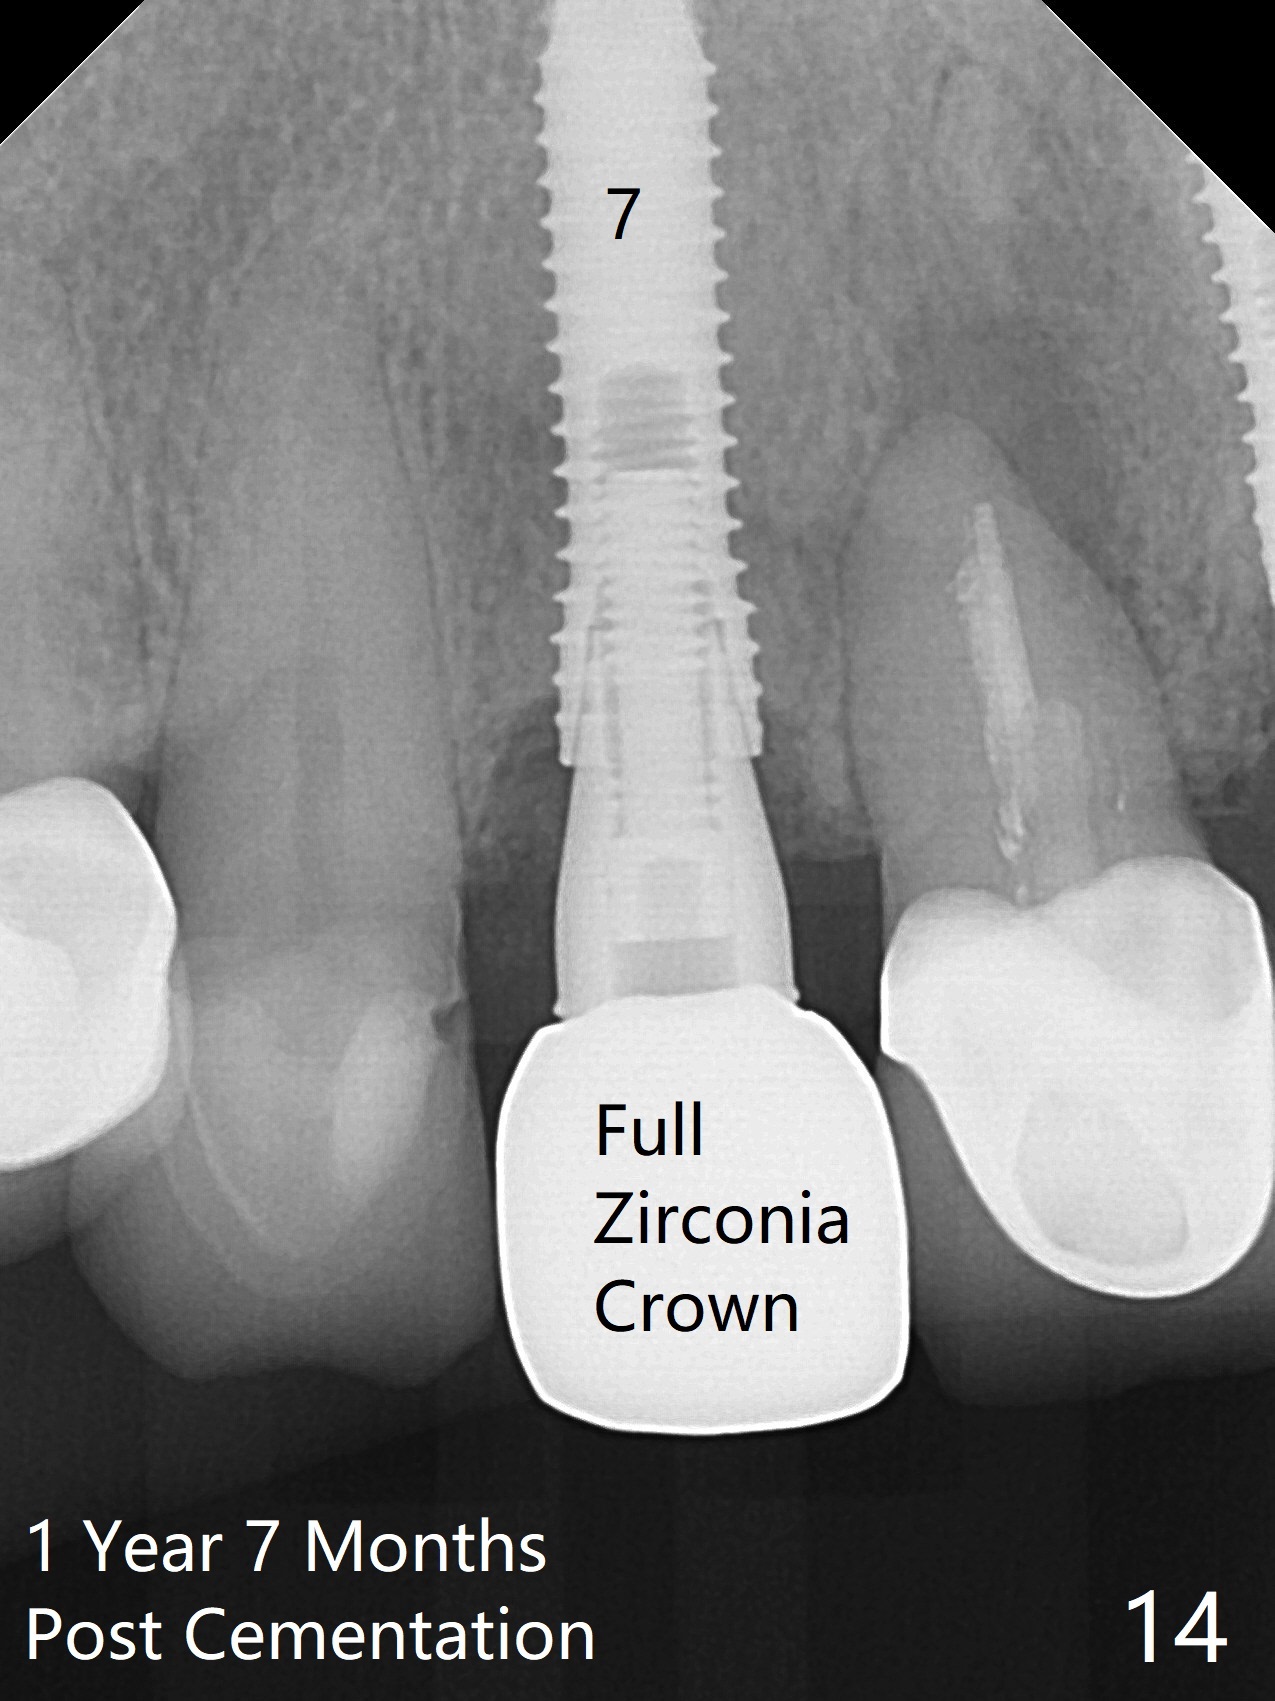

Nasal Floor

The buccal contour at #9 seems to be slightly concave preop (Fig.1,2 (*)). In fact the buccal plate is found to be lost when the tooth is extracted. Osteotomy is initiated as palatal as possible apical, but the occlusion dictates the coronal end of the osteotomy should be buccal, leaving the buccal gap ~ 2 mm for bone graft. The initial osteotomy (18 mm deep) appears to be close to the Incisive Foramen (Fig.3 blue dashed line). The nasal floor appears to be intact when the drill is removed. Subsequent osteotomy is adjusted so that the apical end of the osteotomy moves distal; when a 3.8x15 mm dummy implant is partially placed, there is clearance (Fig.4). It remains so when a definitive implant is seated (Fig.5); Vanilla graft is placed (Fig.5 *) before placement of a 4.5x5.5(3) mm abutment. More allograft is placed when an immediate provisional is fabricated (Fig.6 arrow and *). The gingiva remains to be recessive 1 month postop (Fig.7). It seems to be related to the bulky gingival margin of the provisional (Fig.8 *). After trimming the latter (Fig.9 *), the gingival margin immediately returns close to normal (Fig.10). The gingival margin is even between #8 and 9 two months postop, but the bone graft is exposed apically (Fig.11 ^). It may heals by itself. Otherwise debridement, regraft, PRF and suture are pending. The coronal portion of the socket heals 4 months postop (Fig.12). The gingival cuff forms by the immediate provisional (which is removed for impression) 4 months postop (Fig.13 *). While the full Zirconia crown at #7 remains intact (Fig.14), the PFM at #9 has porcelain chip (Fig.15). It is partially due to the occlusion; while the crown at #7 has clearance with the opposing dentition (Fig.16 *), the one at #9 has no. The access hole at #9 (Fig.17 *) seems to weaken the crown structure. There is no access hole at #7. No solid posterior support is another contributing factor for chip (Fig.18). The buccal plate has mild atrophy at #7 and 9 (Fig.19 *). A piece of bone graft is being expelled apically at #9 (Fig.20 >) and is removed subsequently (Fig.21). Before impression for repacking porcelain, the opposing incisal edge has been shortened (Fig.22 arrows, as compared to Fig.16). Since the ideal access hole is at the incisal edge (Fig.25 black circle), buccal to the existing one (Fig.24 A), the abutment is torqued before the repaired crown is recemented (Fig.23). Finally the crown has occlusal clearance (Fig.26). Porcelain chips again around the access hole of PFM 1.5 years post 2nd cementation. The dense bone at the crest (*) cannot explain why the abutment is not loose, since it remains incompletely seated (>). As it was trimmed short, an angled abutment is used (Fig.28). The coronal end is lingual, while #9/24 is edge to edge. The lingual aspect of the coronal end of the abutment is heavily trimmed to reduce bulkiness. To prevent chip, Zirconium crown will be fabricated in spite of the fact that it does not match the PFM of #8 (potential shade discrepancy). The patient is pleased with the new Zirconia crown (Fig.29).